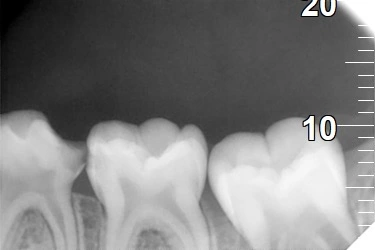

The tooth had a severe infection. The plan was to remove the infected pulp (pulpectomy). The canals were cleaned with small rotary files. They were filled with a safe, resorbable paste (Metapex). A stainless steel crown was placed to protect the tooth and restore chewing.

Day 1: Exam, X-ray, and start of pulpectomy (access opening)

Day 2: Remove pulp, clean canals, and fill them with Metapex.

The child was calmed using the Tell-Show-Do method. Numbing gel and a local shot made the area pain-free. A rubber dam kept the tooth dry and clean. The decay was removed. The infected pulp was taken out. The canals were cleaned and filled. A stainless steel crown was fitted and cemented.